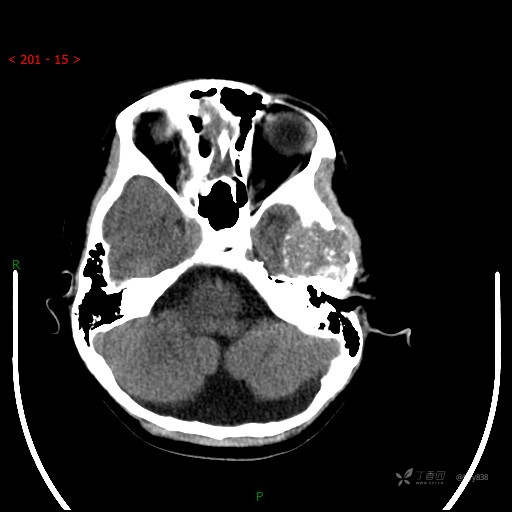

“典藏”病例分享。10岁儿童,头痛头晕一周余,CT、MRI 都有---结果公布~

简要病史:患者于一周前无明显诱因开始出现头痛头晕,无恶心呕吐,无肢体抽搐,无寒颤高热,无腹胀腹泻,无视力下降及视野缺损,上述症状休息后可稍缓解,未引起重视。 2天前患者头痛头晕不适加重,伴有恶心感,无呕吐,遂到当地人民医院行头颅CT检查示:左侧颞部占位性病变,今日家属为求进一步治疗,来我院门诊求治。门诊拟“左侧颞部占位性病变”收入我科。 患病以来,患者精神、饮食、睡眠尚欠佳,大小便如常,体力体重无明显变化。

临床诊断:左侧颞部占位

颅脑CT扫描